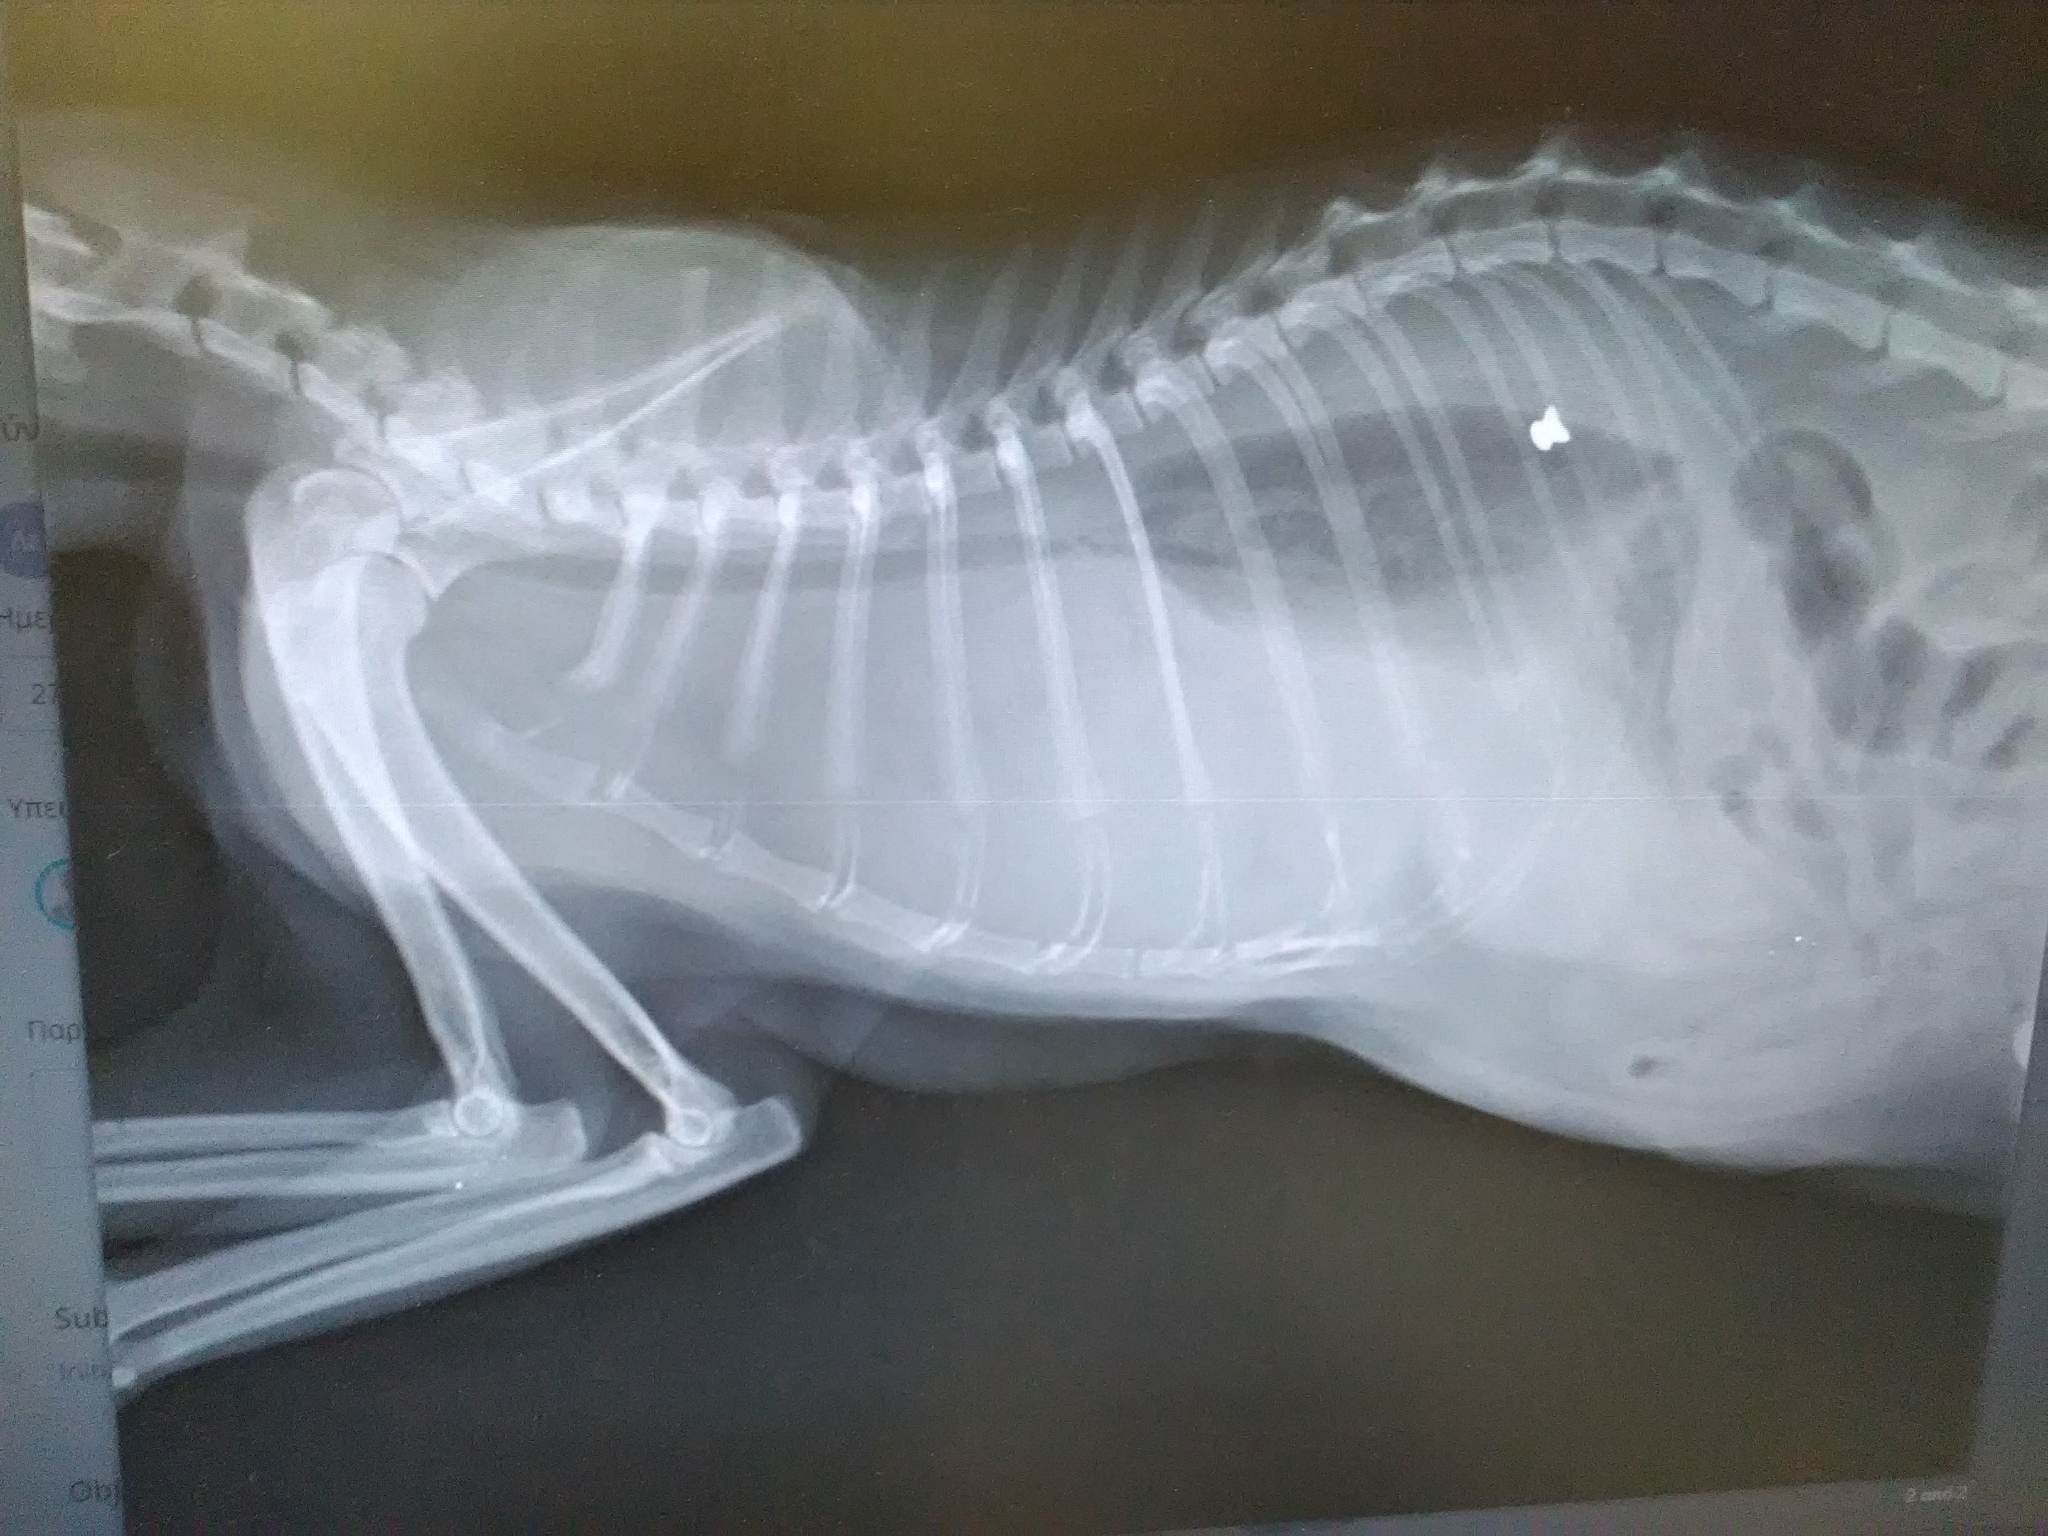

Στα τραύματα της υπέκυψε σήμερα η γάτα που εντοπίστηκε πυροβολημένη την Κυριακή 26 Φεβρουαρίου. Το ζώο μετέφερε στο κτηνιατρείο του Βασίλη Χριστόπουλου στην Κοζάνη ο Στέργιος Κυράτζης και εκεί η ακτινογραφία έδειξε τι υπέστη το ζώο. Το σφαιρίδιο του αεροβόλου είχε καρφωθεί στον πνεύμονα του ζώου. Όπως μας εξήγησε ο κ. Κυρατζής κατέθεσε καταγγελία κατ’ αγνώστου στο Α.Τ. Γρεβενών.

KaliraxiGrevenonGataPyrovolimeniAerovoloAktinografia27 2 2023 3Η ακτινογραφία έδειξε το σφαιρίδιο του αεροβόλου καρφωμένο στον πνεύμονα της γάτας...